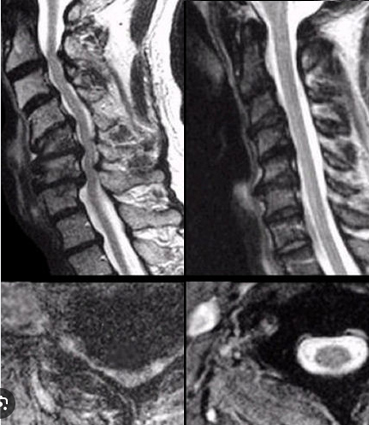

Estenose de Canal